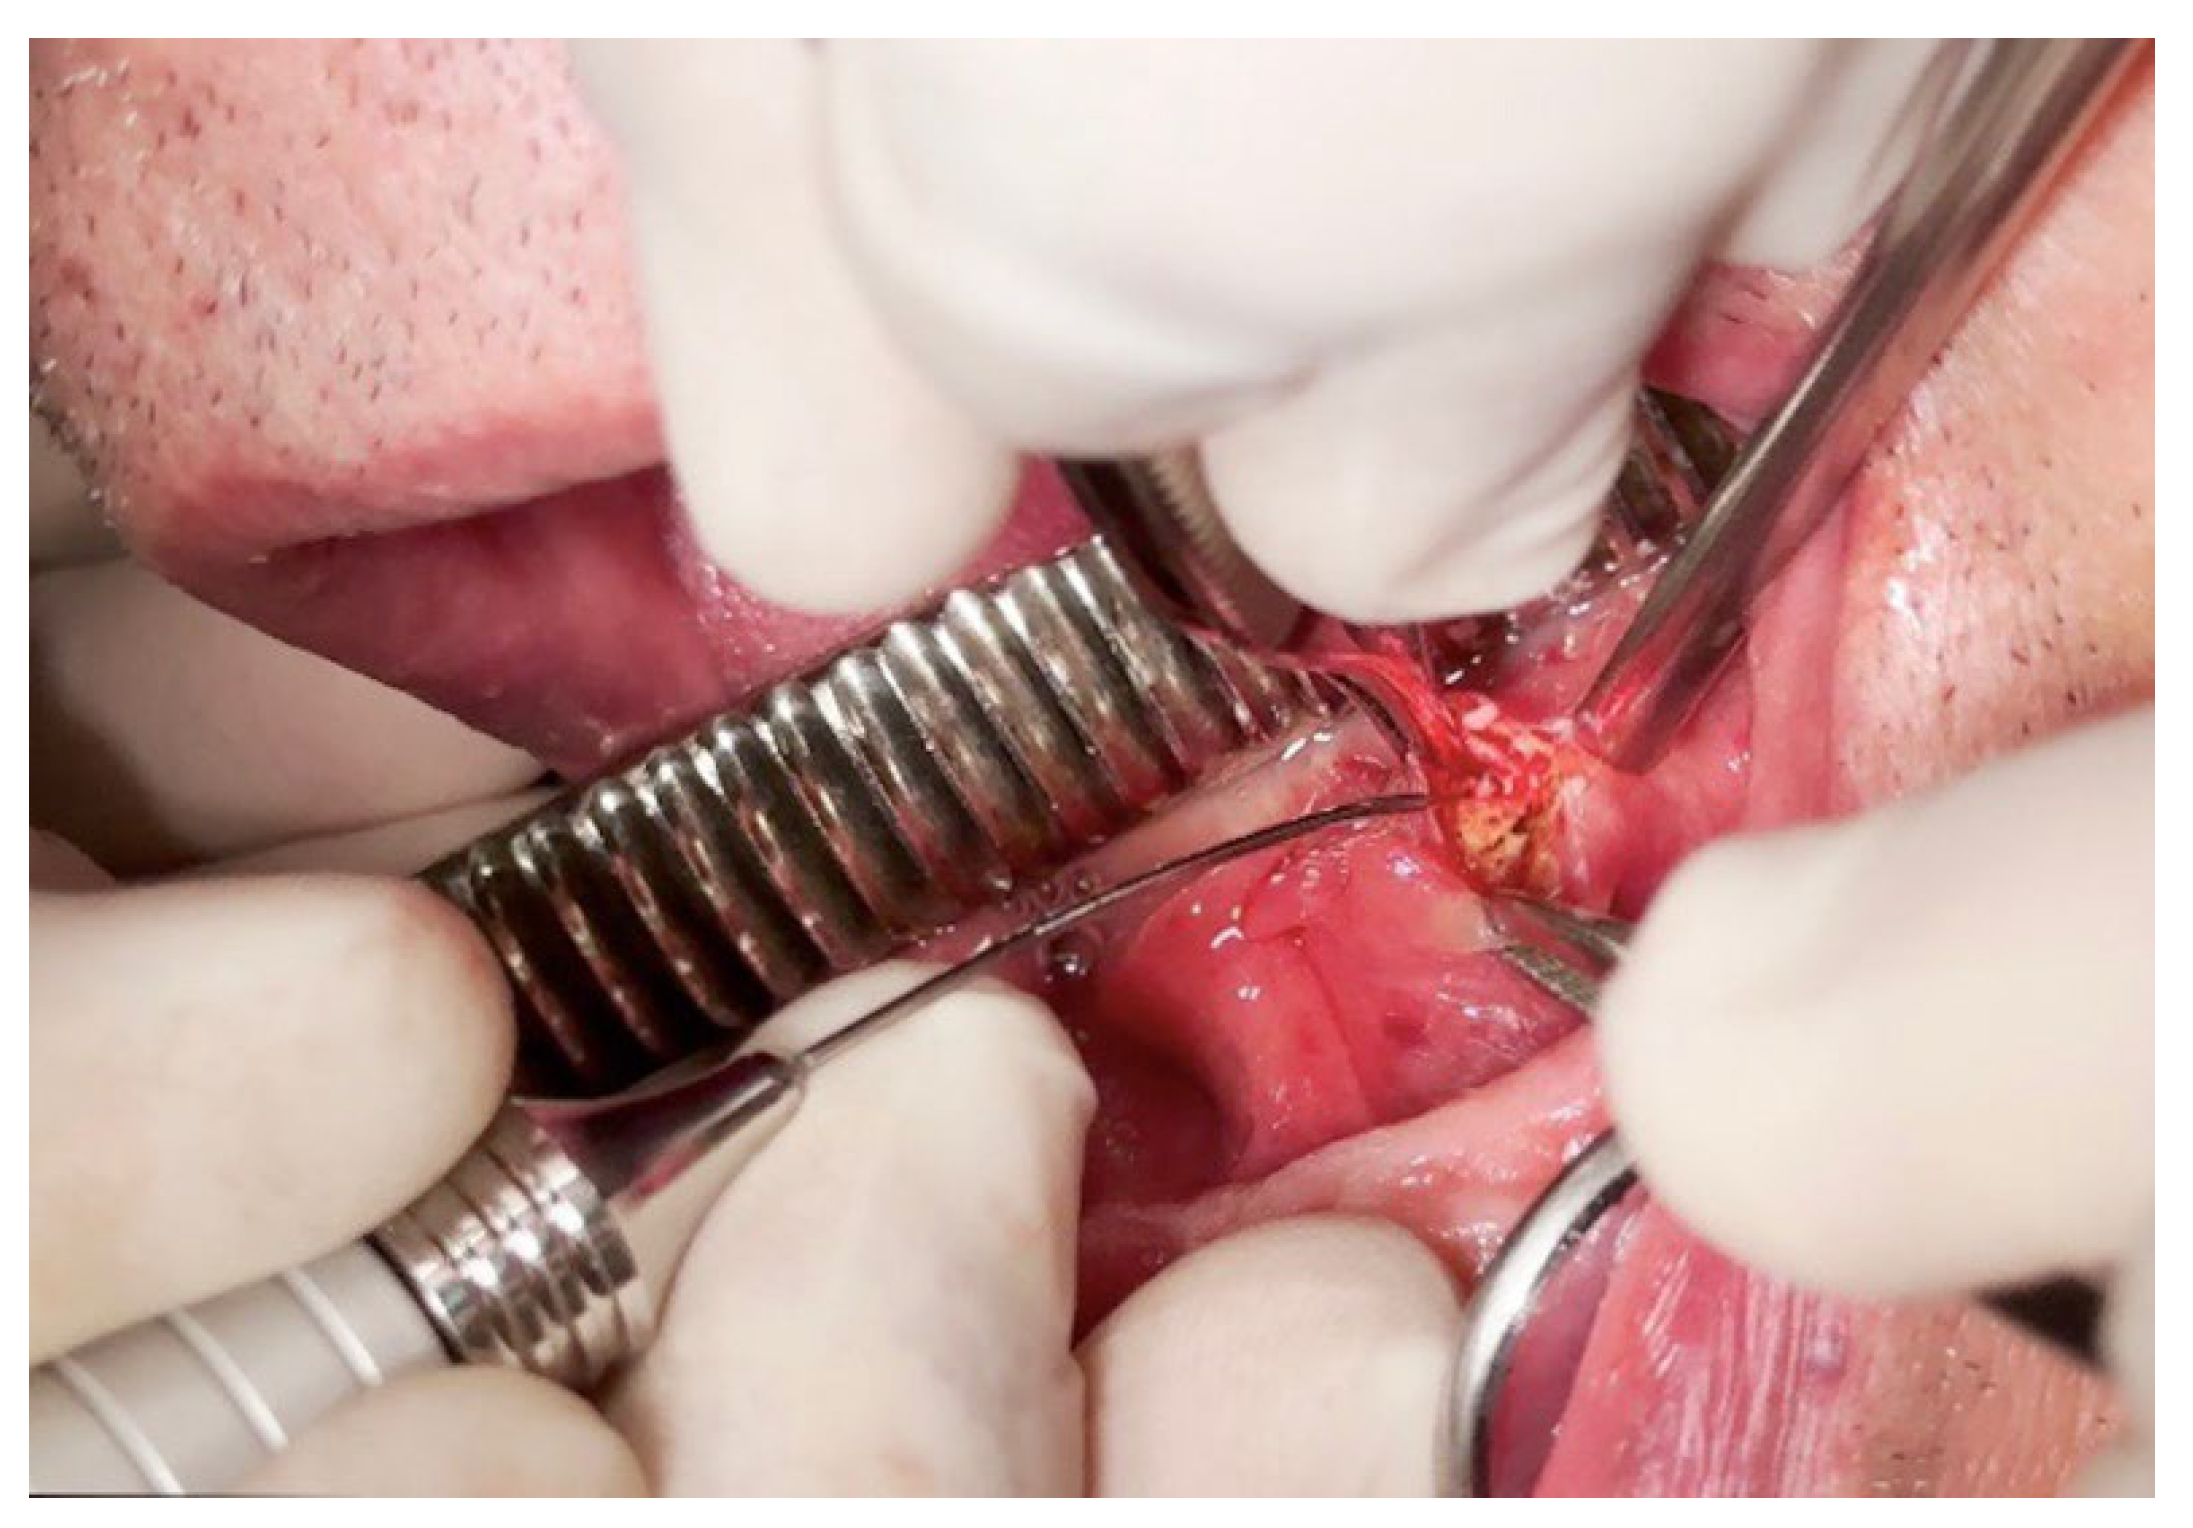

| Kılınç et al. (2014) [16] | Case report | 1 cases, 1F: 57Y |

In the anterior part of the left side of the floor in the mouth. | Diode Laser | 810 nm of wavelength, 4.0 W of power, 0.5 ms continuous wave and 1000 Hz of frequency was selected. | Antibiotic: Amoxicillin clavulonate 1000 mg , every 12 h for 5 d. Rovamycine every 12 h for 5 d). Anti-inflammatory: 100 mgr flurbiprofen every 12 h for 3 d | No sign of infection was observed, and salivary flow was normal. | 10th days. | An 810-nm diode laser is a safe and effective technique, offering excellent cutting and coagulation with a low complication rate, making it suitable for this surgical procedure. |

| Angiero et al. (2008) [17] | Case series | 25 cases. | Wharton’s duct | Diode laser | Wavelength of 810-830nm ,2,5W CW with 5-10 sec irradiation time (energy density 12,5-25J,, flexible fibre 300-320 em | None of the patients required analgesic therapy | Postoperatively, three patients experienced odynophagia, impaired mouth opening, and submandibular swelling, which subsided in 2-3 days. | For up to 6 years. | It Is a valid alternative to traditional surgery |